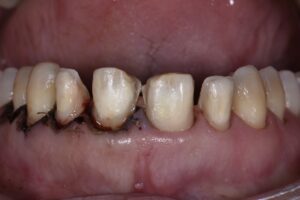

This nice 54 year old female desired a correction of her occlusal and gingival cant with simultaneous correction of the midline cant.  She rejected the option to complete gingivo-osseous recontouring at a separate appointment with a 2-3 month healing period as she had seen a previous case completed featuring osseous recontouring and preparations at the same time with good predictability.  The old Cerec leucite reinforced glass ceramic restorations were overcontoured and covering excessively prepared teeth along with exposed margins cervically.  A Digital Smile Design was completed for the patient indicating the extent of areas to be modified to gain near complete correction of the gingival and occlusal cant without being overly aggressive.

Following initial preparation from teeth 9-12 (2.1-2.4), the margins were located equigingivally.  From this point, the DSD was used as a guide to the change in cervical profile which was accomplished initially using the Ultradent Gemini diode Superpulsed laser at 1.2W in dual-wavelength mode.  The margins were relocated to this level, and a transsulcular approach using a Kois Wedelstaedt chisel was attempted and was generally successful except for a few problematic areas where re-establishment of ideal crestal distance from the margins was dubious.  A full thickness envelope flap was raised and the offending areas directly osteoplastied using the Kois Surgical System (Brasseler) prior to debriding the area and gaining primary closure using vertical mattress sutures.